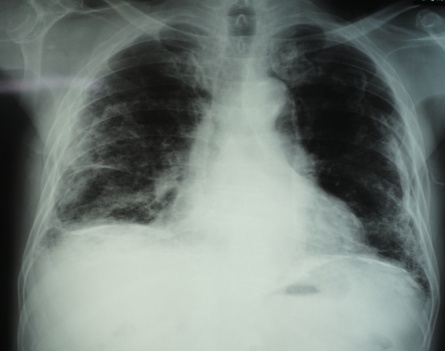

5. 初回XP/CT胸膜プラーク無・最新回XP無・CT有は3名で【写真3】胸膜プラークの確認時年齢は69・77・80歳、80歳時点の胸部CTはプラーク検出に有意義だった。

【写真3】初回CT胸膜プラーク(-)最新回CT(+)

胸部X線写真で胸膜プラークのある場合、胸膜プラークは経年的に厚く大きくなり徐々に石灰化した【写真1】。胸膜プラークはCTで66~80歳で初めて認められ、70台,80才の胸部CT写真撮影の必要性が認められた【写真3】。高濃度石綿ばく露をうけた23名中4名に80台でも胸部CTで胸膜プラークのない群が確認された。肺がんによる死亡が3名に認められ、胸膜プラーク有は1名で2名はXP・CT共に最後までプラークなしだった。職業性石綿ばく露を受けた集団は、退職から永眠までの期間の健診体制を必要とし、胸部X線CT写真を併用し観察する意義が再確認された5)